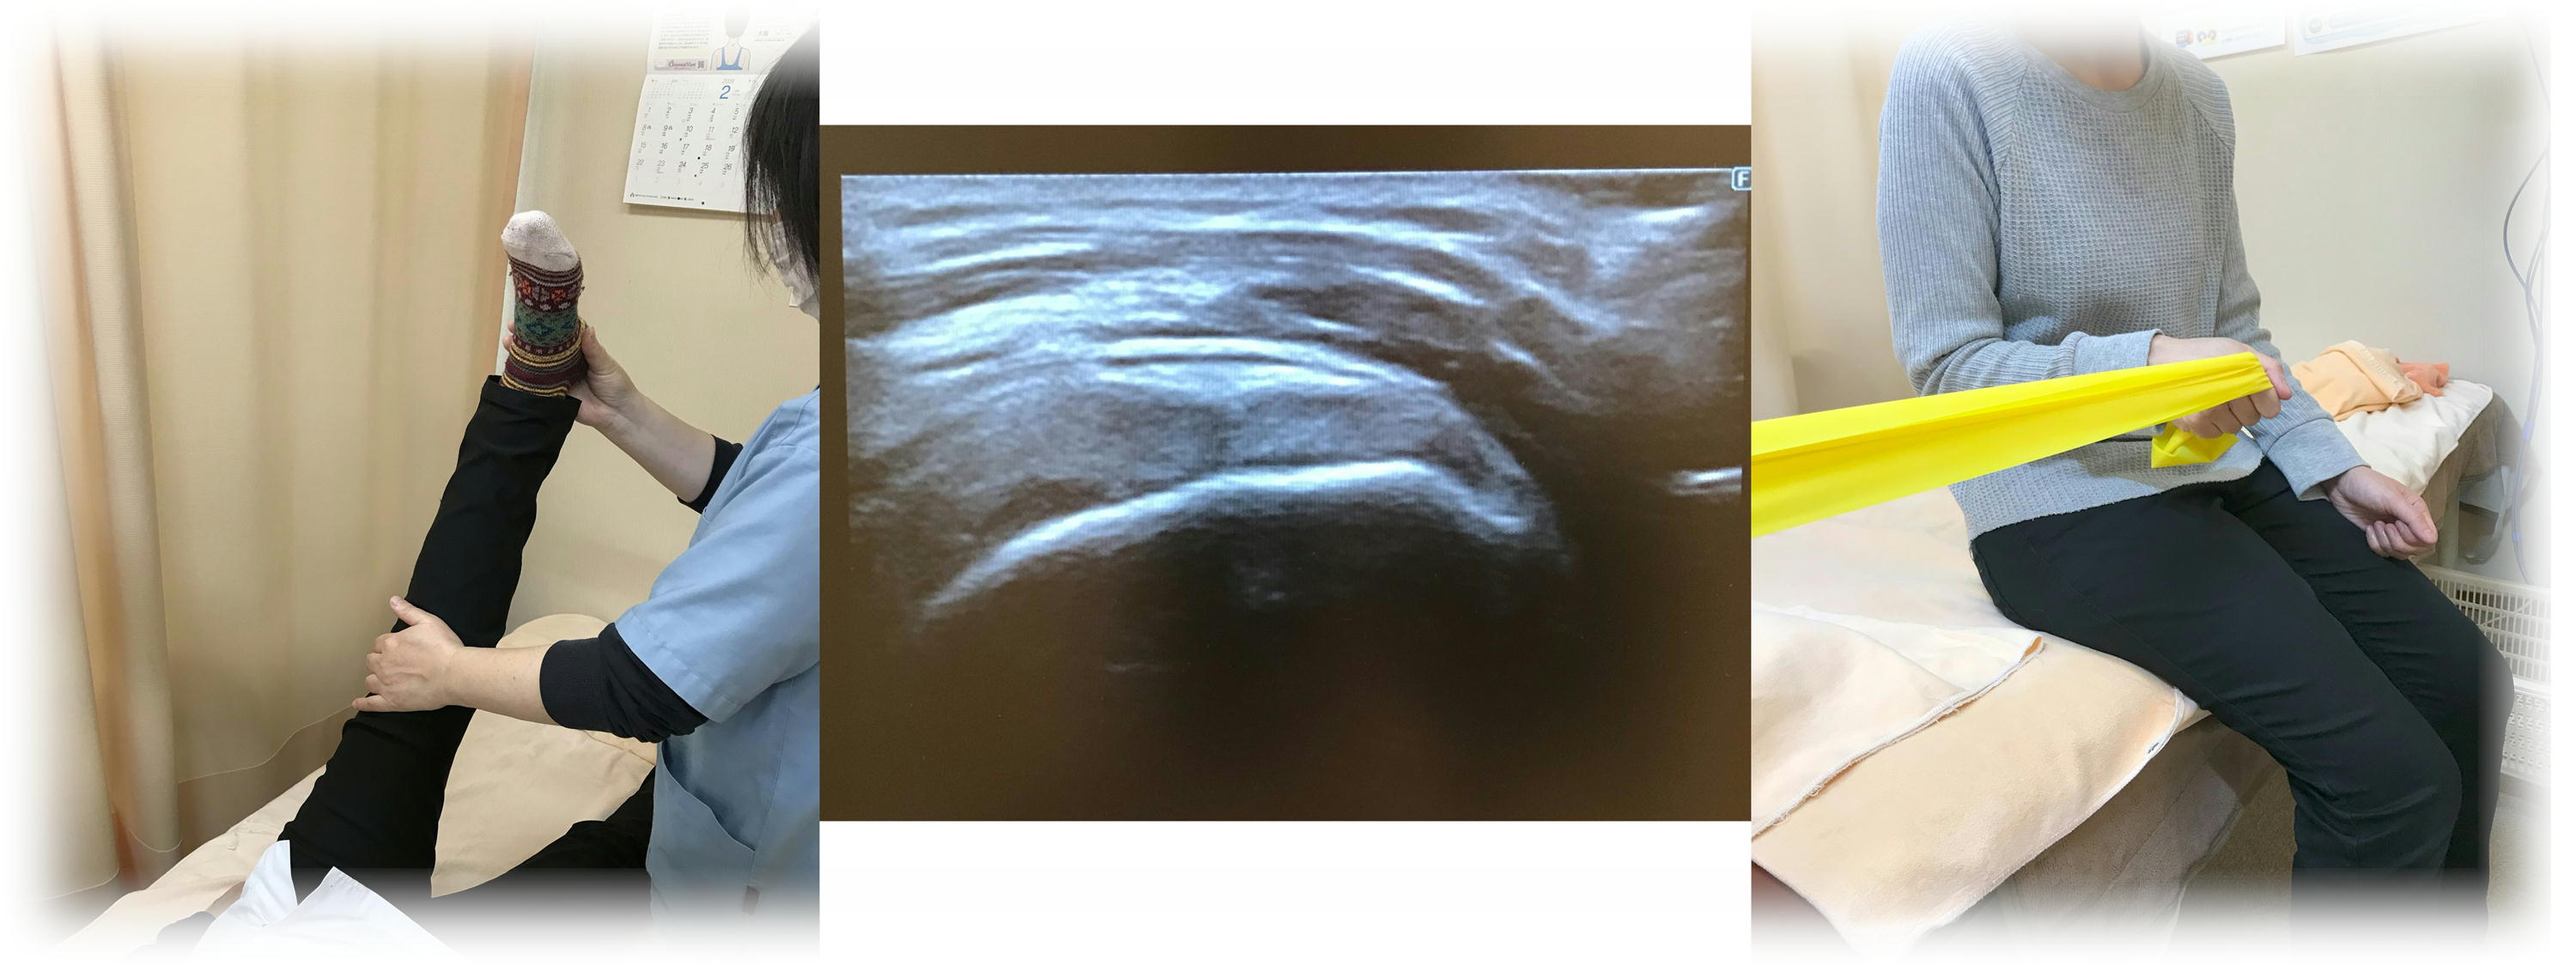

- 施術内容

- 「小学生~高校生までの成長期」で野球・ソフトボール・ハンドボール・テニス・器械体操など、「投球や肘に負担をかける競技」をしている子どもに。

- 成長期は骨が柔らかいため、無理を続けると筋肉より「骨が」痛んでしまい、最悪「骨折」という事態に。そうなると、将来の競技人生に影響を及ぼす場合があります。そのため、こまめに肘の状態をチェックすることが大事です。肘の骨の状態をエコーでチェックして、確認していきます。

- ※肘以外も「膝のオスグッド」なども見ておりますので、気になる方はご相談ください。

- ¥1000